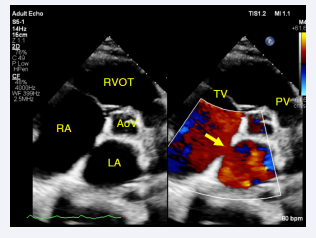

and at mid interatrial septum (IAS), there is an atrial septal defect (ASD) secondum type measuring ~ 15 mm with QP/QS 3.1 flow from left to right by color Doppler (Figure 3,4)

Two-dimensional TTE, parasternal short-axis, aortic valve  level, demonstrates a dilated RA, a large ASD secundum type (arrow)  with left-to-right flow by color Doppler. RVOT, Right Ventricle Outflow  Tract: AoV, Aortic Valve: TV, Tricuspid Valve: PV, Pulmonary Valve.

Figure 3: Two-dimensional TTE, parasternal short-axis, aortic valve level, demonstrates a dilated RA, a large ASD secundum type (arrow) with left-to-right flow by color Doppler. RVOT, Right Ventricle Outflow Tract: AoV, Aortic Valve: TV, Tricuspid Valve: PV, Pulmonary Valve.

Two-dimensional TTE, apical 4-chamber view with color  flow Doppler, systolic phase, demonstrates a large ASD (arrow) with a  longitudinal diameter of 15.6 mm.

Figure 4: Two-dimensional TTE, apical 4-chamber view with color flow Doppler, systolic phase, demonstrates a large ASD (arrow) with a longitudinal diameter of 15.6 mm.